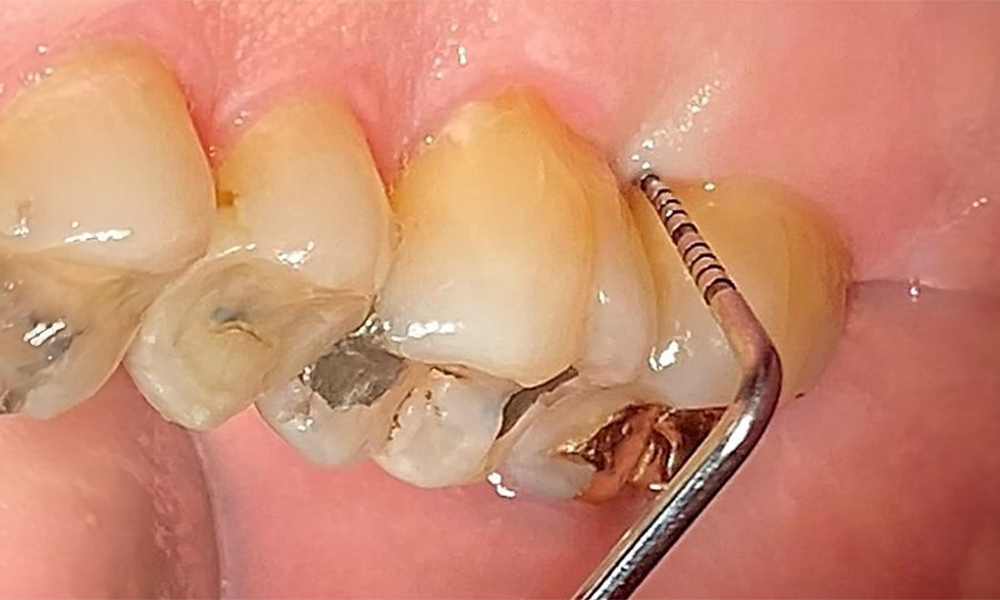

The documentation of periodontal findings, including pocket depth probing and bleeding status, is mandatory during each dental appointment due to the presence of periodontitis (Fig. 8). This will record the individual therapeutic needs and facilitate a rapid response to any progression of the pre-existing periodontitis.

Probing to document the findings in tooth 27 mesiopalatal. © Dr R. Krapf

Fig. 8: Probing to document the findings in tooth 27 mesiopalatal. © Dr R. Krapf